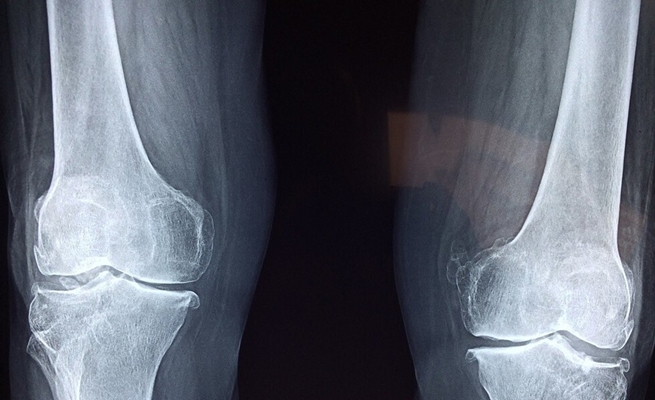

وعملوا معا لإعادة استخدام المواد النانوية للبحث عن الخلايا الجذعية الموجودة في الهيكل العظمي البشري وإثرائها، والتي يمكن أن تحدث ثورة في علاجات إصابات العظام وربما إصلاح أو استبدال العظام المفقودة.

وهذه الخلايا العظمية لم تُرمّز بعد لوظيفة محددة، وبالتالي يمكن إعادة استخدامها لإنماء وإصلاح أنسجة العظام والغضاريف بهدف إصلاح العظام المكسورة.